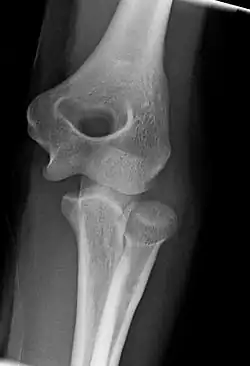

Right: AP X ray of a dislocated right elbow

The types of disease most commonly seen at the elbow are due to injury.

There are three bones at the elbow joint, and any combination of these bones may be involved in a fracture of the elbow. Patients who are able to fully extend their arm at the elbow are unlikely to have a fracture (98% certainty) and an X-ray is not required as long as an olecranon fracture is ruled out.[27] Acute fractures may not be easily visible on X-ray.[28]

Dislocation

Elbow dislocations constitute 10% to 25% of all injuries to the elbow. The elbow is one of the most commonly dislocated joints in the body, with an average annual incidence of acute dislocation of 6 per 100,000 persons.[30] Among injuries to the upper extremity, dislocation of the elbow is second only to a dislocated shoulder. A full dislocation of the elbow will require expert medical attention to re-align, and recovery can take approximately 6 weeks.